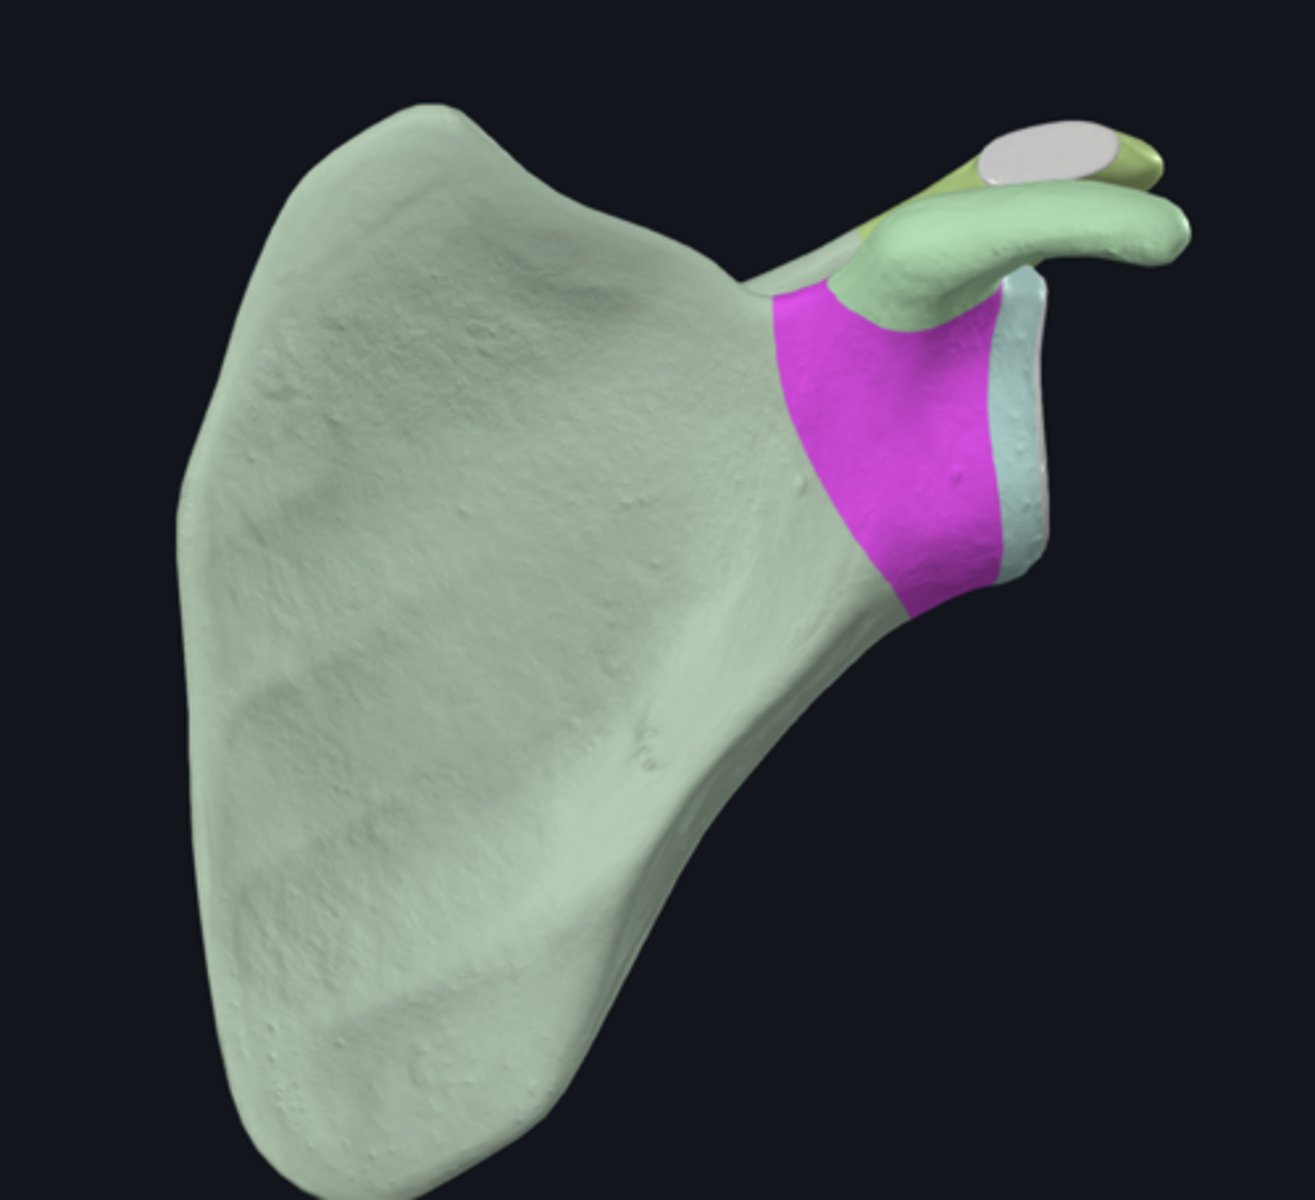

Acromion

Coracoid process

scapular notch

superior border of scapula

acromial angle

clavicular facet

glenoid fossa

infraglenoid tubercle

infraspinous fossa

spine of scapula

supraglenoid notch

subscapular fossa

supraglenoid tubercle

supraspinous fossa